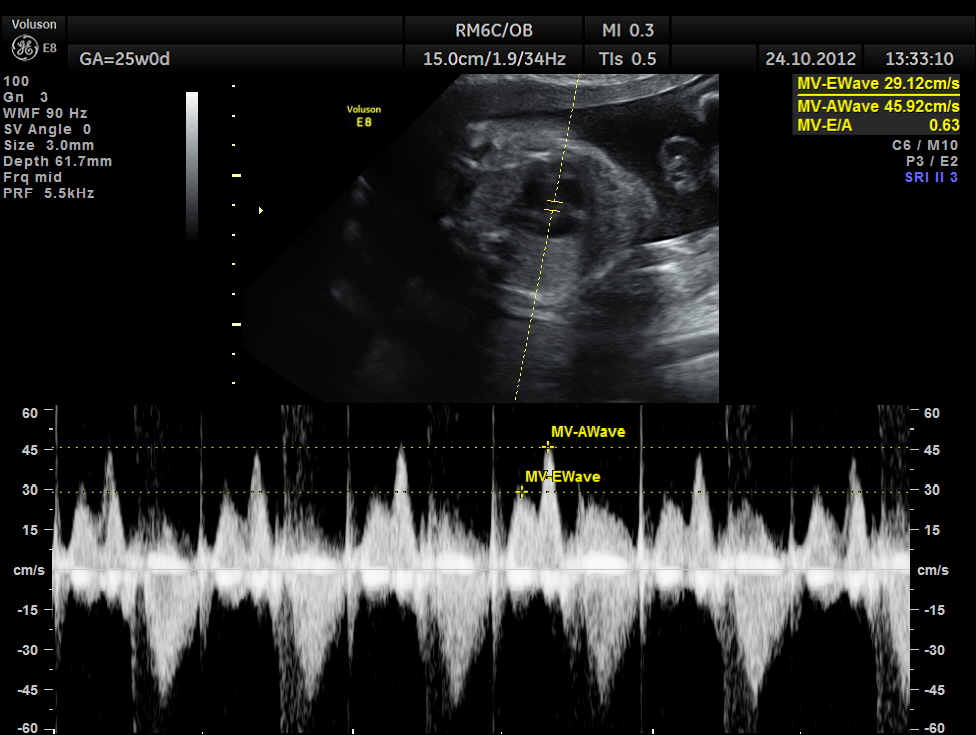

The scan was done around 25 weeks of gestation :

the following are spectral doppler flow across the 4 valves